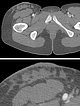

In the corresponding computed tomography, the lymphatic malformation with its fluid deposition and connective tissue component appears somewhat more hyperdense than the surrounding subcutaneous adipose tissue. The overall soft tissue contrast is poorer than in MRI. There is also no contrast enhancement on CT. Note in the detail enlargement (bottom image) the thickening of the skin due to the cutaneous microcystic portions of the LM.